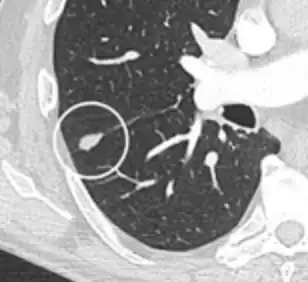

- A lung nodule abutting a pulmonary cyst is a rare finding, yet indicating cancer.[9]

- Bubble-like lucencies in the nodule indicate cancer:[9]

- Vascular convergence is where vessels converge to a nodule without adjoining or contacting the edge of the nodule, and is mainly seen in peripheral subsolid lung cancers.[9] It reflects angiogenesis.[9]

Air bronchograms is defined as a pattern of air-filled bronchi on a background of airless lung, and may be seen in both benign and malignant nodules, but certain patterns thereof may help in risk stratification.[9]